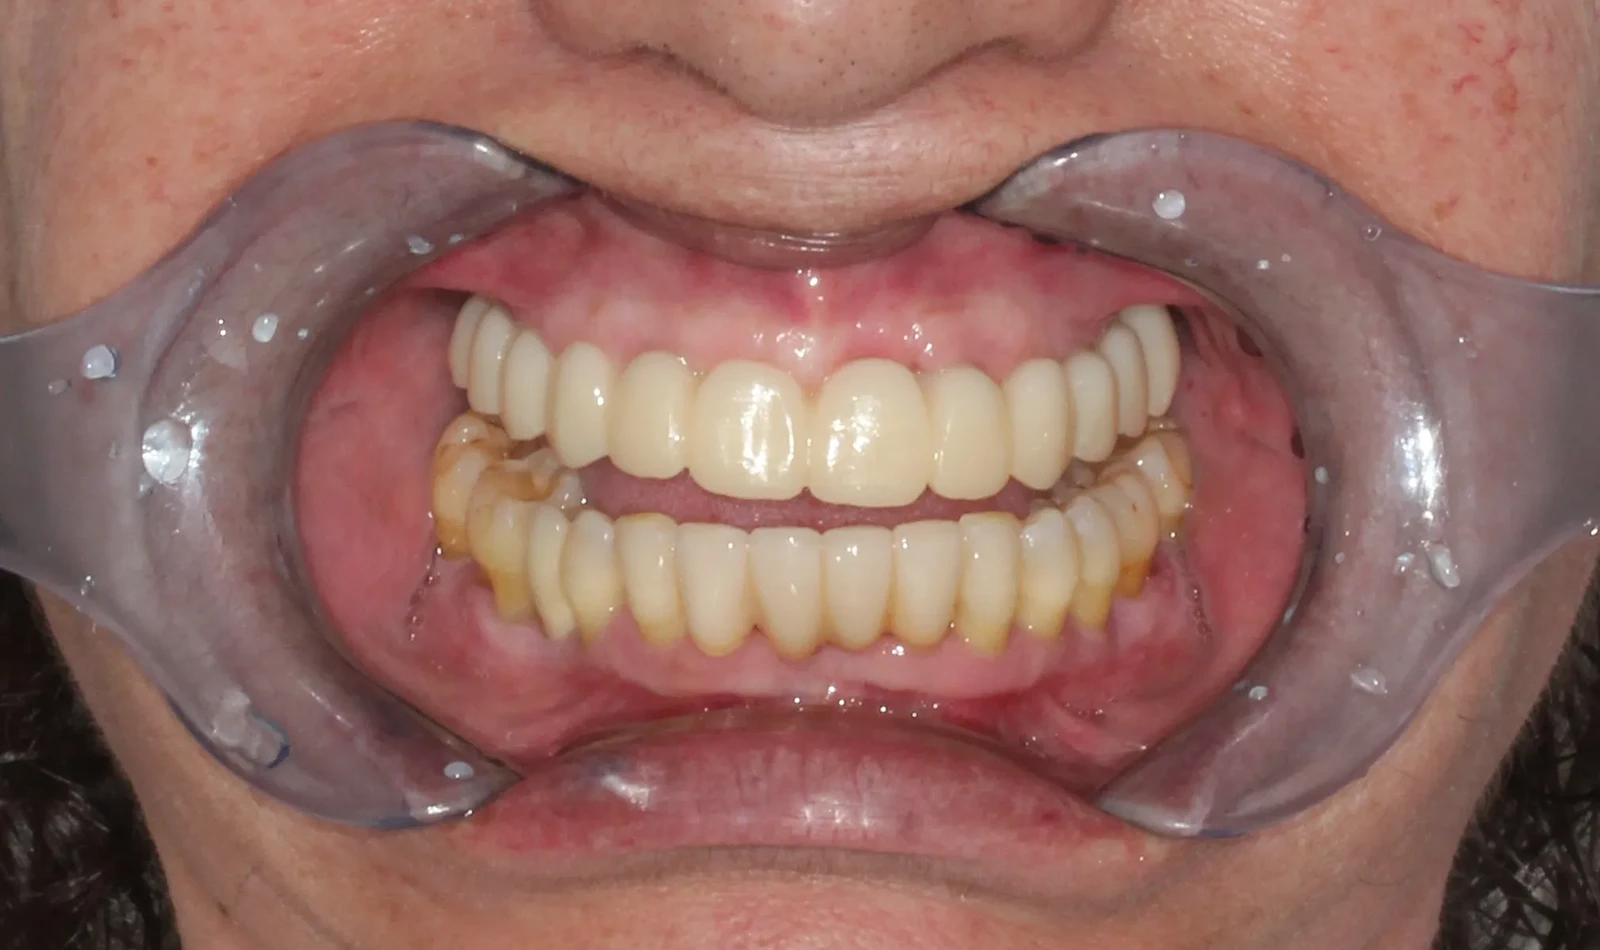

Paciente de 60 años, sufría porque sus dientes se movían y temía perderlos todos, pero gracias a la cirugía guiada y la técnica de carga inmediata, en un solo día Merche recuperó una sonrisa fija y natural. Volvió a comer, hablar y sonreír con mayor comodidad desde el primer momento.